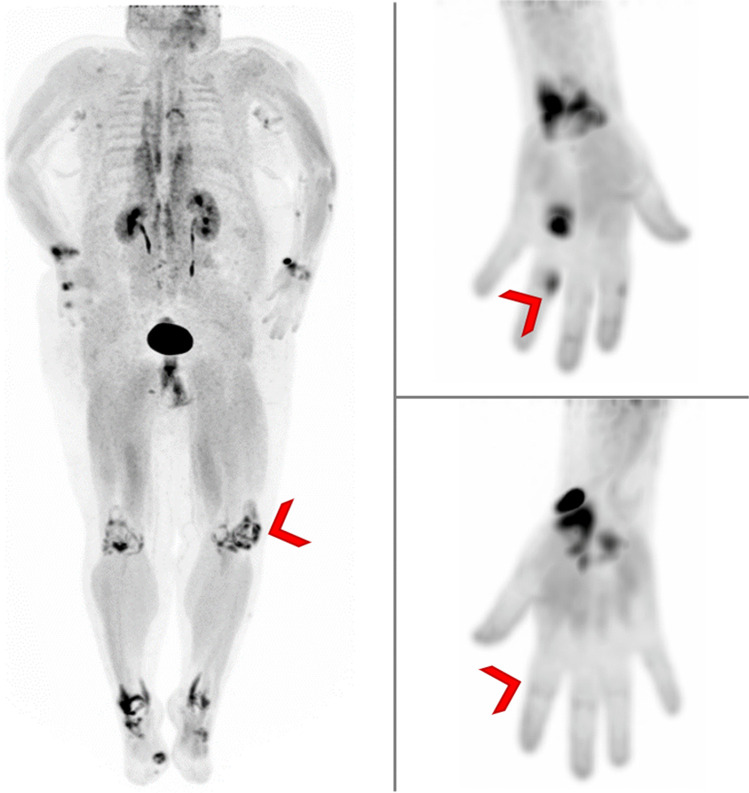

Imaging molecular processes associated with inflammatory disease has been revolutionized by hybrid imaging using positron emission tomography/computed tomography (PET/CT). PET/CT visualizes metabolic activity as well as protein expression and provides a comprehensive whole-body evaluation. It has the potential to reveal inflammation prior to detection of structural changes in inflammatory joint diseases. FAP is a type II transmembrane glycoprotein overexpressed not only in the stroma of tumors but also in the fibrotic processes of certain immune-mediated disorders. The recent introduction of fibroblast activation protein inhibitors (FAPI) labeled by positron emitters and thus suitable for PET/CT allows to investigate FAP expression in vivo. This review will focus on the use of FAPI-PET/CT for the diagnosis and evaluation of treatment response in inflammatory joint diseases.